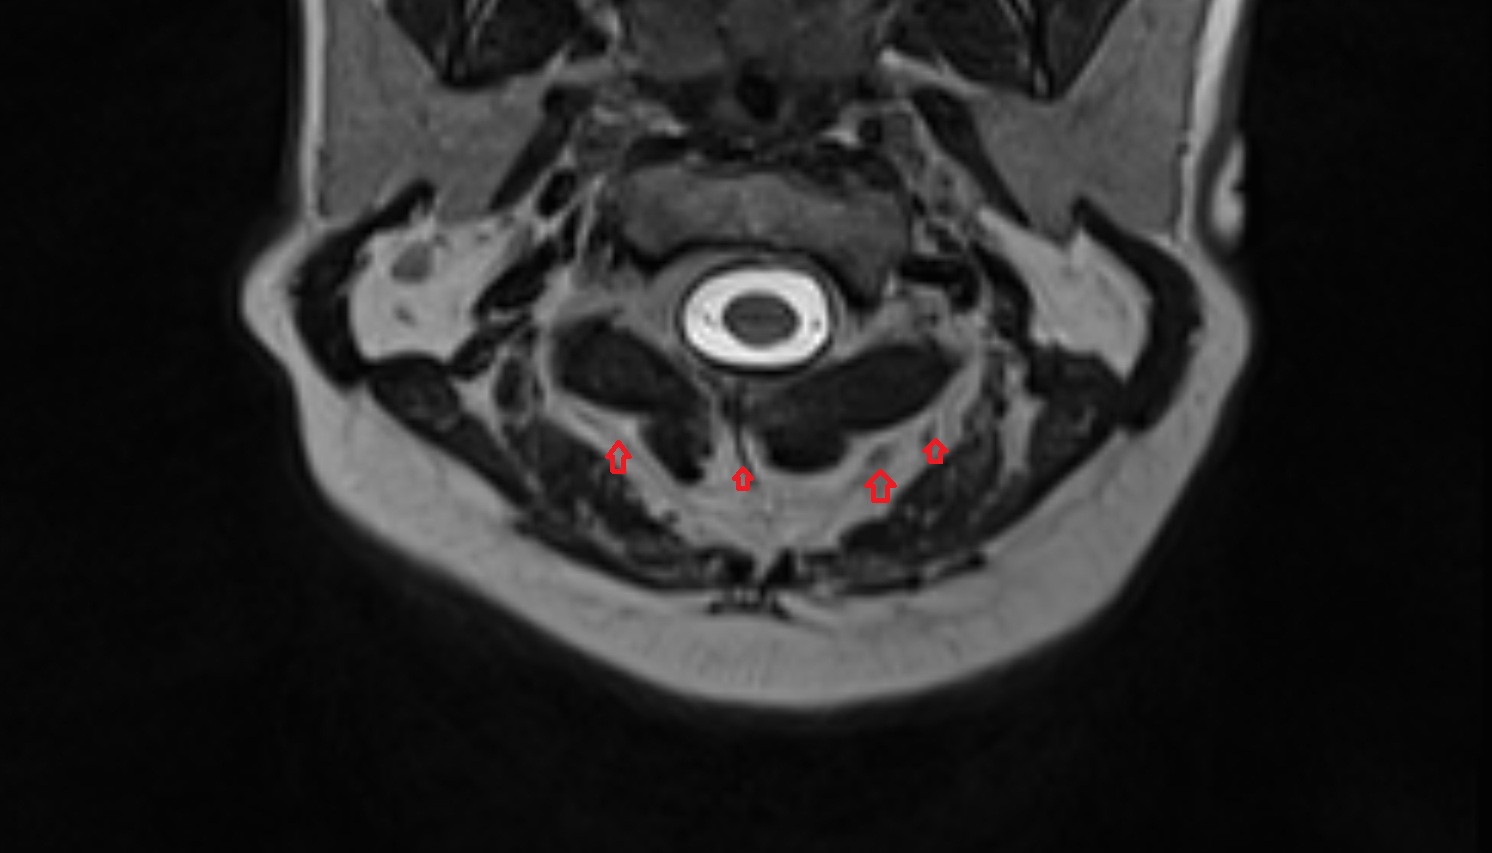

- Peripheral zone of prostate

- Anterior Fibromuscular Stroma of prostate

- Central zone of prostate

- Transitional zone of prostate